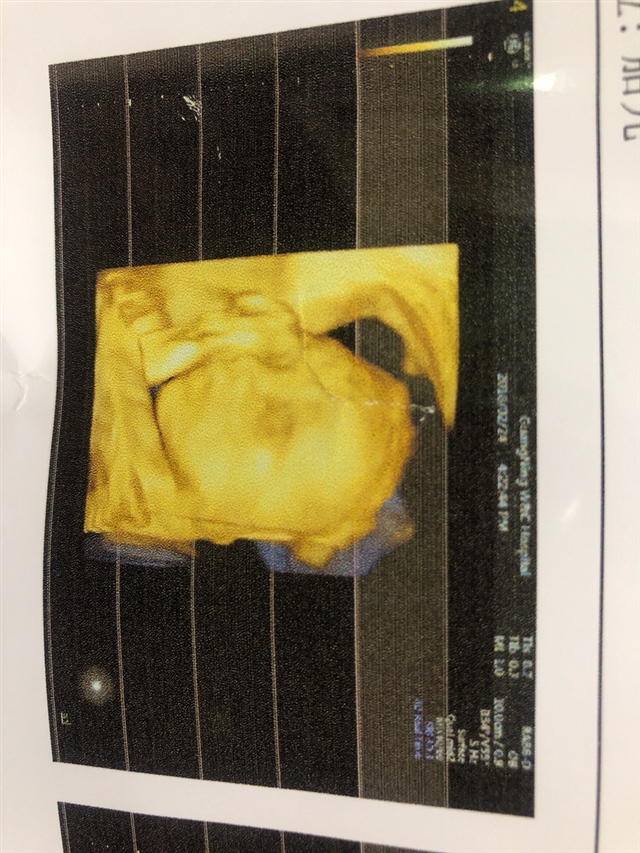

产前检查 B超